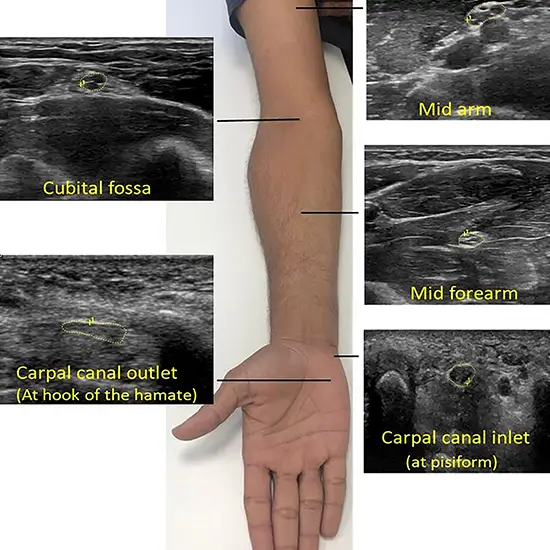

An ultrasound test uses ultrasonography to examine the big arteries and veins in the forearm using blood flow in the arms or legs.

This ultrasound examination examines blood flow in the large arteries and veins of the arms and legs. Doppler ultrasonography uses ultrasound to examine blood flow in the major arteries and veins of the arms and legs (high-frequency sound waves that echo off the body).